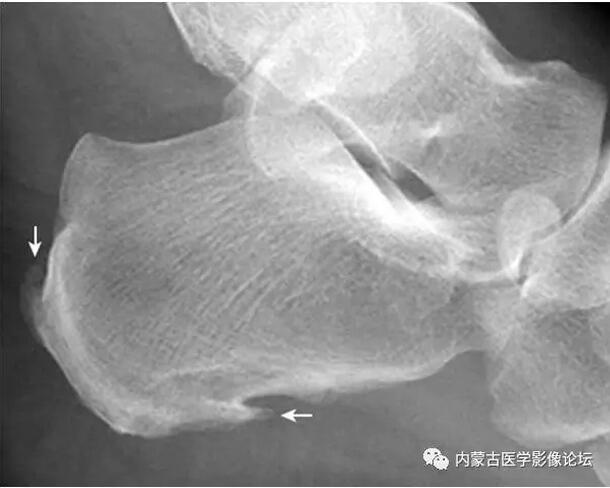

足跟骨刺x光片

足跟骨刺x光片,足跟骨刺图片

1,足跟骨刺.

距骨鼻区撕脱骨折:距骨鼻区见小片状骨性密度影,其与距骨对应处见骨质

足跟骨刺图片

跟骨骨刺